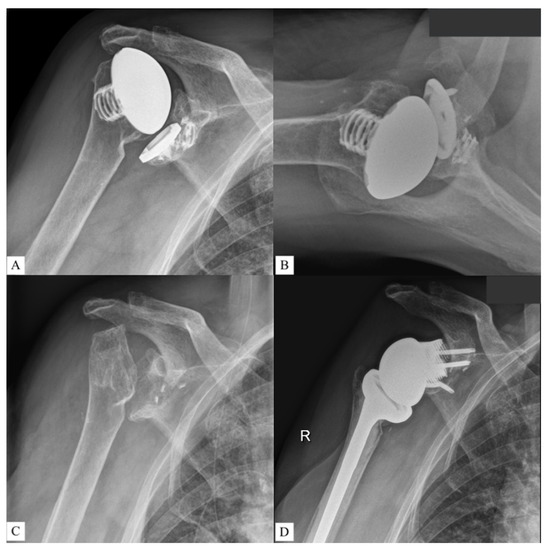

Figure 2. Restoration of the original glenoid surface via statistical shape modelling. Source: planning report provided by Materialise NV, Leuven, Belgium. Reprinted with permission from Materialise. ©2021 Materialise NV.